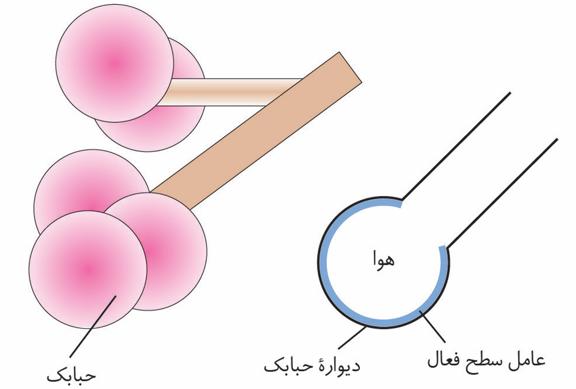

هر کلیه از حدود یک میلیون گُردیزه تشکیل شده است که فرایند تشکیل ادرار در آنها انجام میشود. ابتدای گُردیزه شبیه قیف است و کپسول بومن نام دارد.

بخش قیف شکل کلیه: لگنچه و بومن.

ادامه گُردیزه، لولهای شکل است و در قسمتهایی از طول خود، پیچخوردگیهایی دارد و براین اساس، به قسمتهای مختلفی نامگذاری میشود. این قسمتها به ترتیب عبارتاند از لوله پیچ خورده نزدیک، قوس هنله که U شکل است و لوله پیچ خورده دور که گُردیزه را به مجرای جمعکننده متصل میکند.